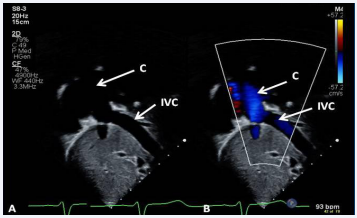

Figure 29: Selected video frame demonstrating wide open conduit (COND) by 2D (A) and color flow imaging (B). Note laminar flow in B indicating no obstruction [69].Figure 30 Selected video frames demonstrating connection between the inferior vena cava (IVC) and the conduit (C) by 2D (A) and color flow imaging (B); note that the IVC–C junction is wide open [69].

Figure 30: Selected video frames demonstrating connection between the inferior vena cava (IVC) and the conduit (C) by 2D (A) and color flow imaging (B); note that the IVC–C junction is wide open [69].

Figure 31 Selected video frame demonstrating low velocity flow between the inferior vena cava (IVC) and the conduit (C) shown in Figure 30, suggesting no evidence for obstruction [69].

Figure 31: Selected video frame demonstrating low velocity flow between the inferior vena cava (IVC) and the conduit (C) shown in Figure 30, suggesting no evidence for obstruction [69].